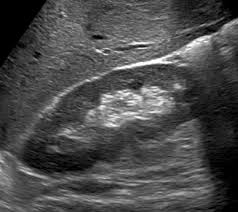

Diagnostic et suivi des grossesses (vitalité, croissance, morphologie).

Exploration de l'utérus, des ovaires et du vagin (par voie externe ou interne si nécessaire).